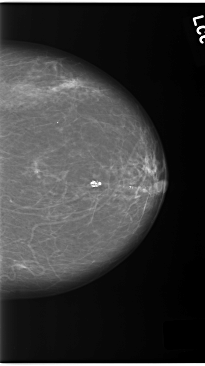

C_0140_1.LEFT_CC

LEFT_CC LINES 5856 PIXELS_PER_LINE 3280 BITS_PER_PIXEL 12 RESOLUTION 50 NON_OVERLAY